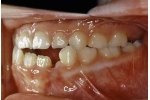

| 初診時